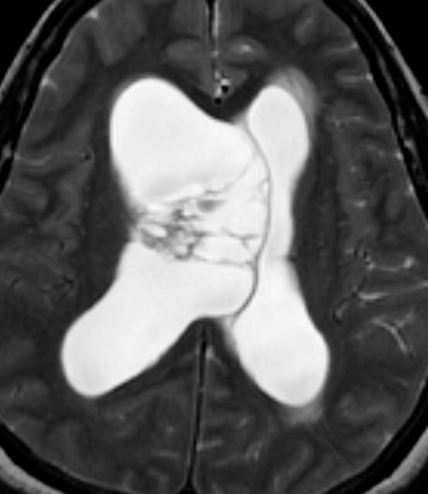

• Masse attaché au septum pellucidum ++

• Proche du Foramen de Monro

• WHO Grade II

• DD subependymome